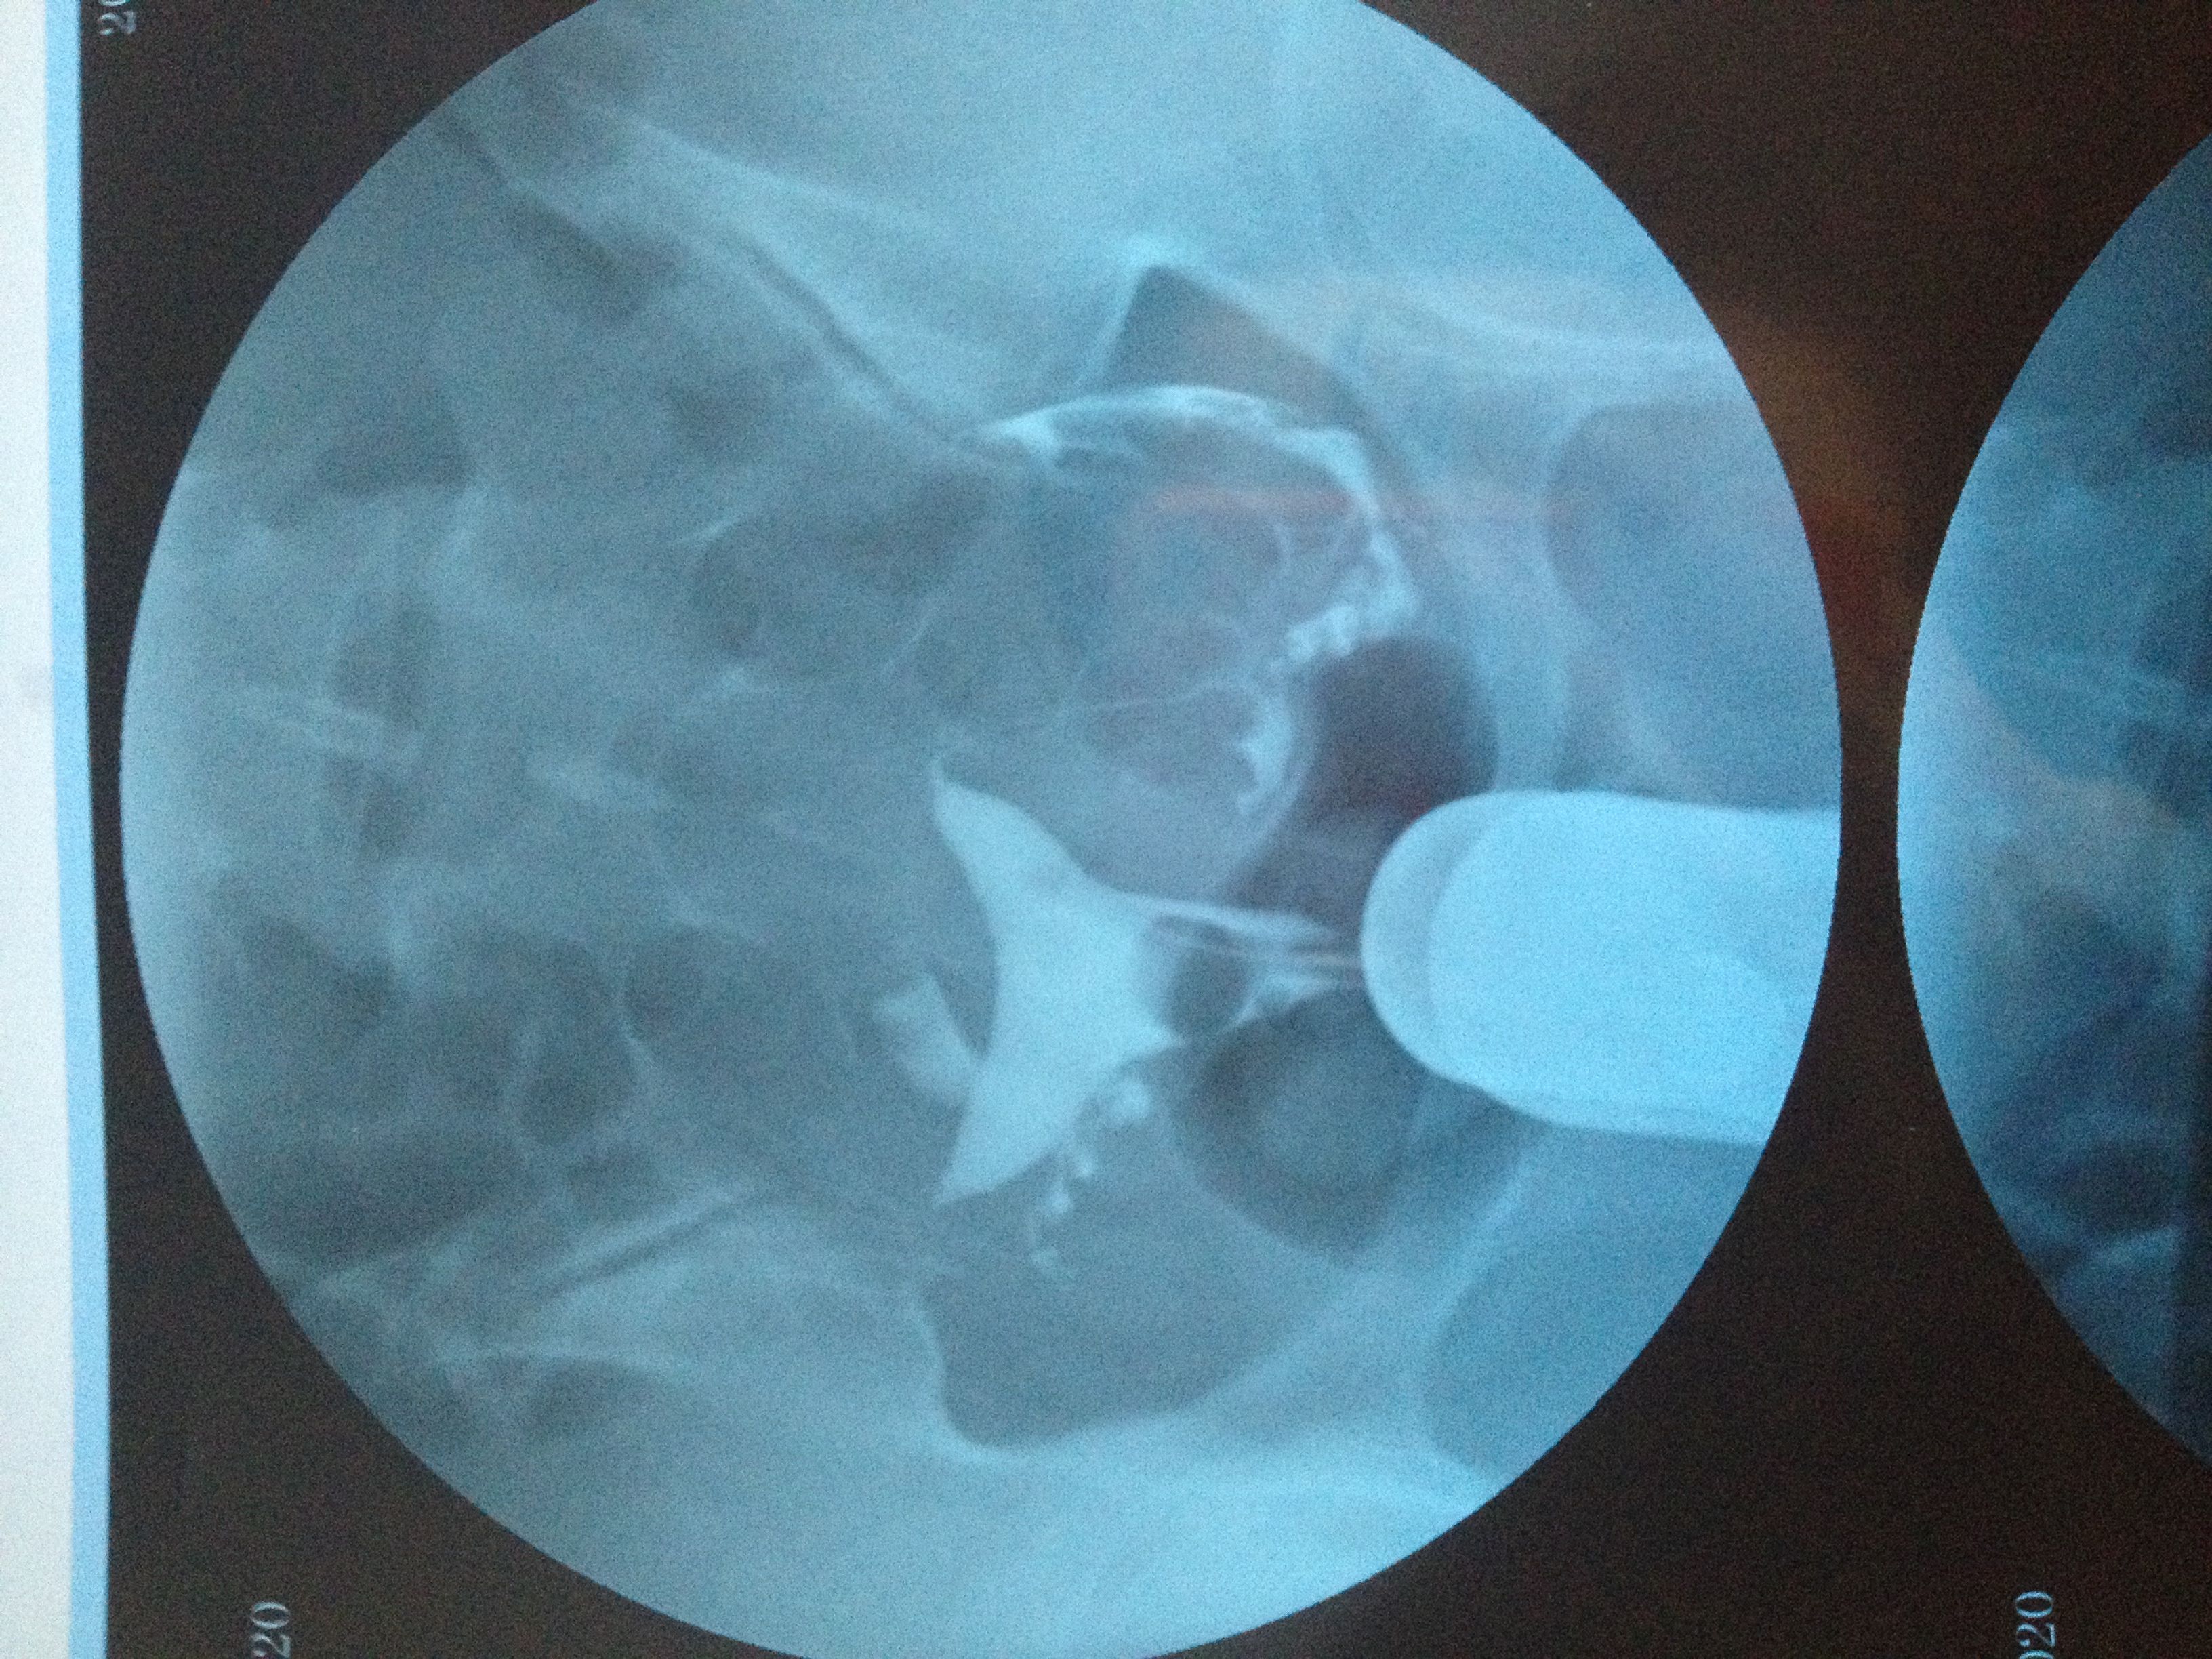

子宫呈鞍形 右侧输卵管走形迂曲 下移 有嵌顿 伞端有照影剂聚集与涌出 左侧走 形略僵直 下移 伞

端有照影剂聚集与涌出 第二次照影盆腔内有等量片状照影剂弥散影响 情况严重吗 应该怎样治疗怀孕呀